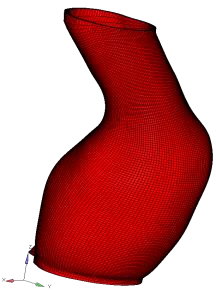

Abdominal Aortic Aneurysm (AAA) is an enlargement in the lower part of the main artery Aorta by 1.5 times its normal diameter. AAA can cause death if rupture occurs. Elective surgeries are recommended to prevent rupture based on geometrical measurements of AAA diameter and diameter growth rate. Reliability of these geometric parameters to predict the AAA rupture risk has been questioned, and biomechanical assessment has been proposed to distinguish between patients with high and low risk of rupture. Stress in aneurysm wall is the main variable of interest in such assessment. Most studies use finite element method to compute AAA stress. This requires discretising patient-specific geometry (aneurysm wall and intraluminal thrombus ILT) into finite elements/meshes. Tetrahedral elements are most commonly used as they can be generated in seemingly automated and effortless way. In practice, however, due to complex aneurysm geometry, the process tends to require time consuming mesh optimisation to ensure sufficiently high quality of tetrahedral elements. Furthermore, ensuring solution convergence requires large number of tetrahedral elements, which leads to long computation times. In this study, we focus on generation of hexahedral meshes as they are known to provide converged solution for smaller number of elements than tetrahedral meshes. Generation of hexahedral meshes for continua with complex/irregular geometry, such as aneurysms, requires analyst interaction. We propose a procedure for generating high quality patient-specific hexahedral discretisation of aneurysm wall using the algorithms available in commercial software package for mesh generation. For aneurysm cases, we demonstrate that the procedure facilitates patient-specific mesh generation within timeframe consistent with clinical workflow constraints while requiring only limited input from the analyst.